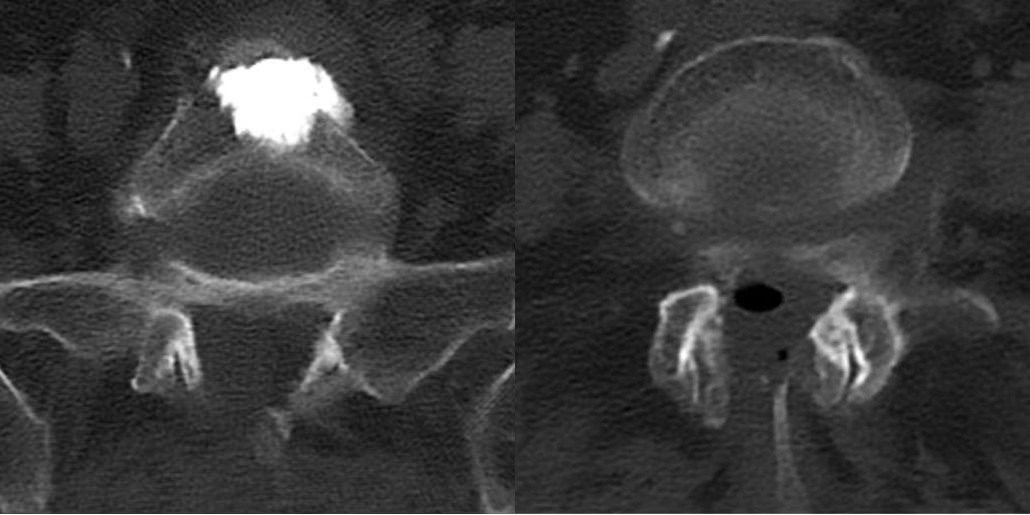

经过3个小时的手术,患者手术顺利,椎体内骨水泥弥散良好,椎管内神经减压彻底。术后患者恢复良好,当天即感觉疼痛缓解。经过2天的术后治疗,患者已经可以正常行走。术后3天,患者平安出院,后续接受康复治疗。

▲术后CT,椎管狭窄较前明显好转